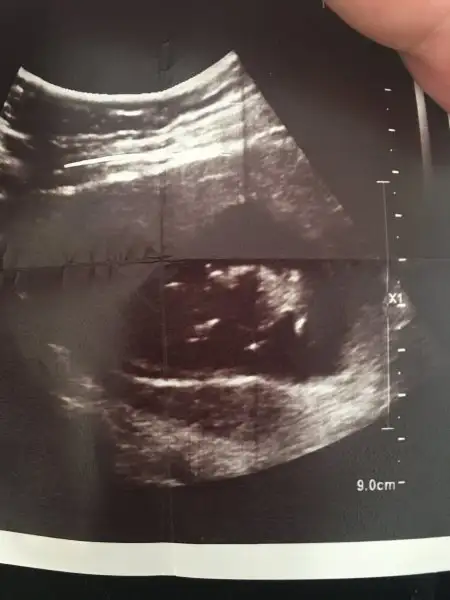

Cinsiyet : ?